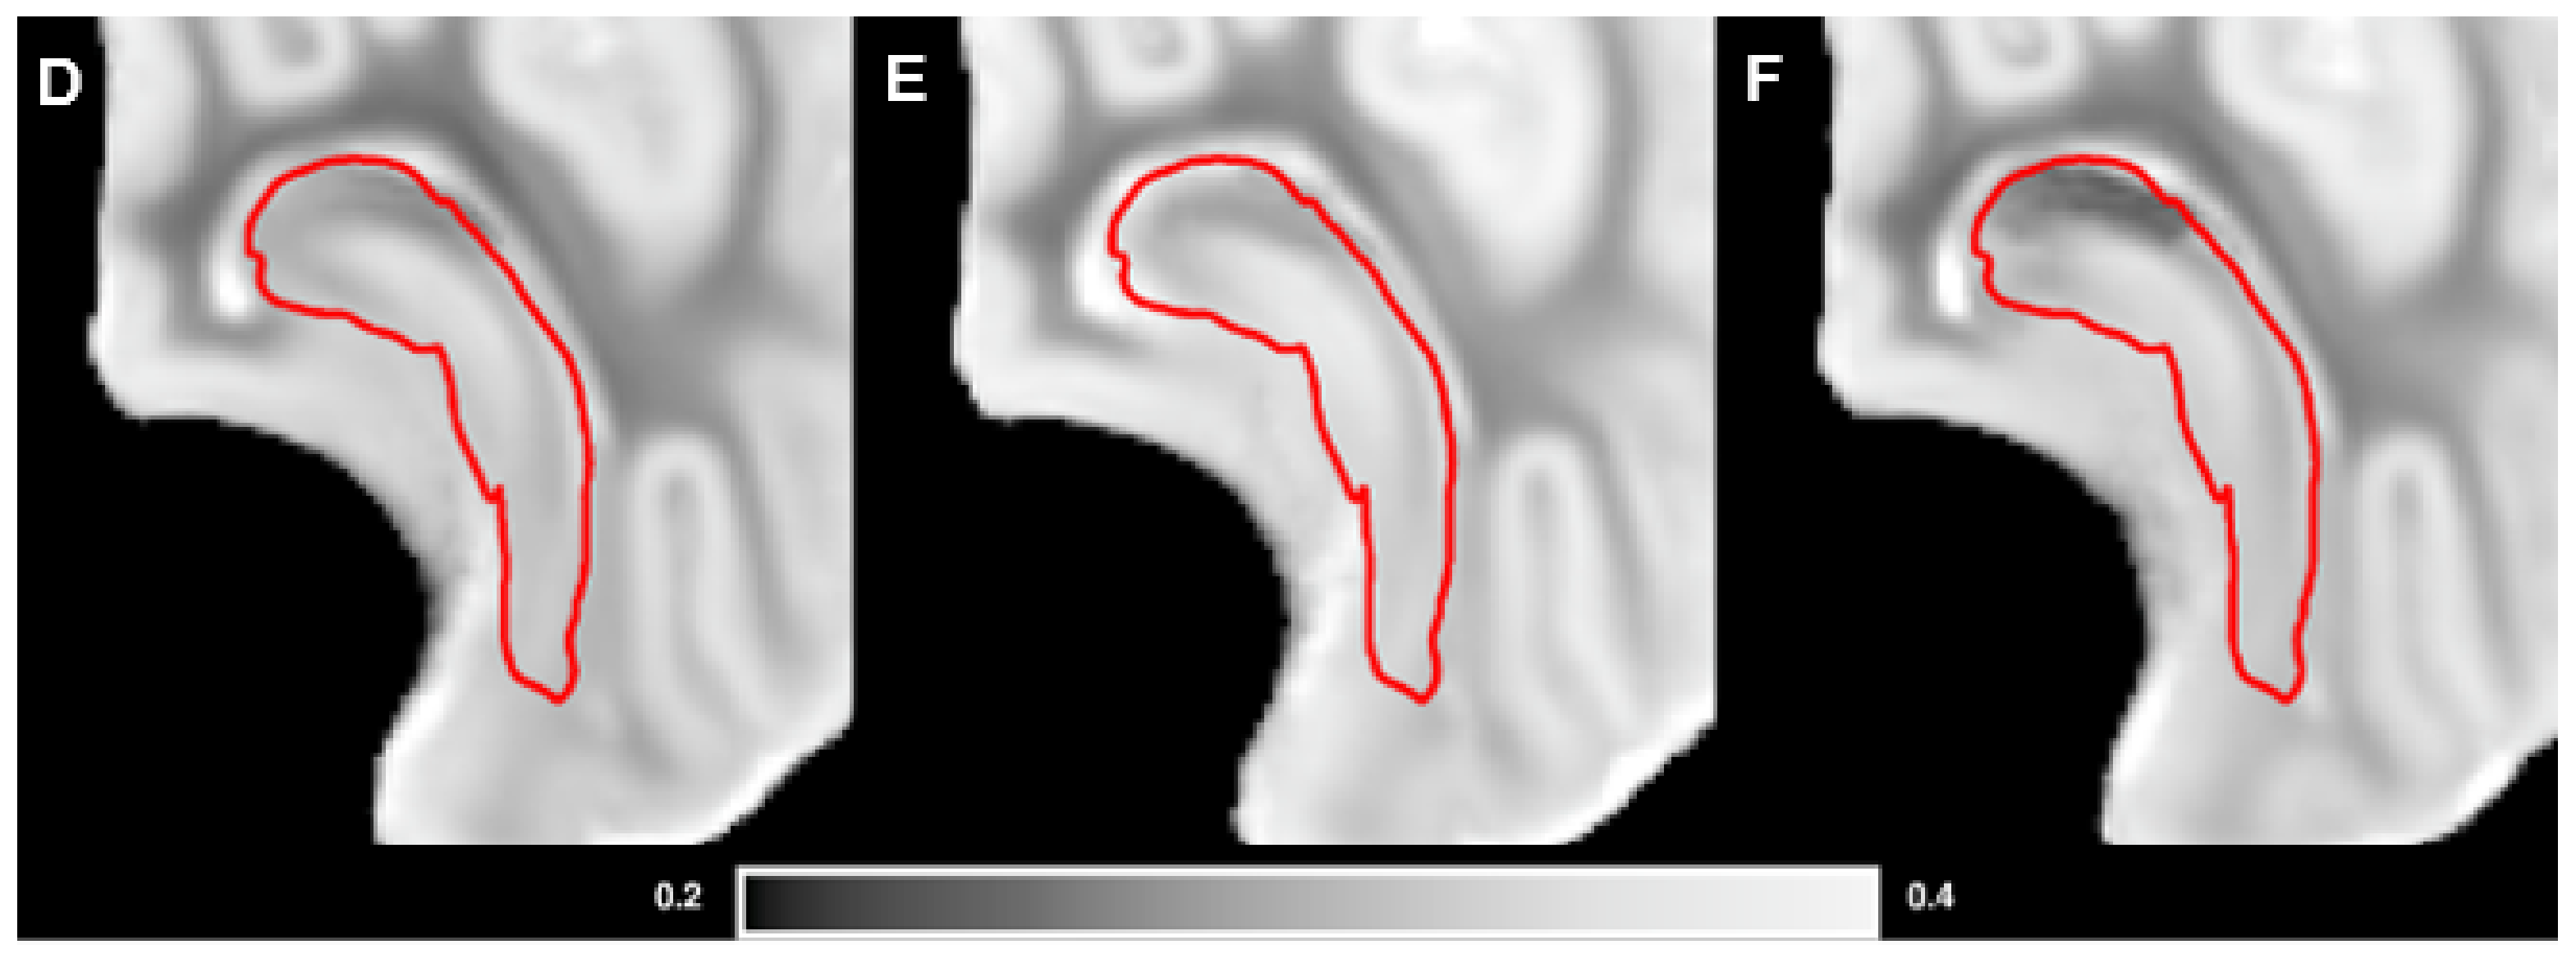

2.5. Magnetic Resonance Imaging

3.3. Brain Weights, Water Content and MRI Analysis